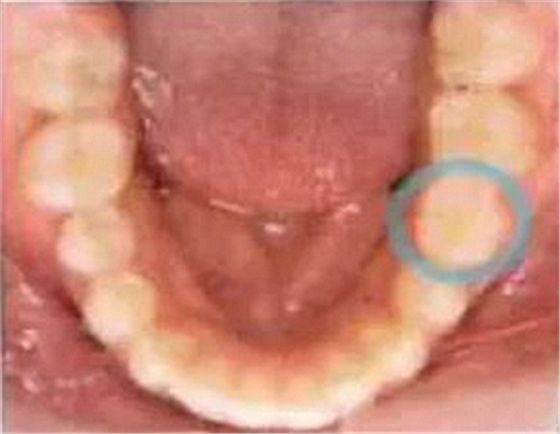

乳牙的晚期殘存(恒牙的先天性缺失)

[原因不明的多顆恒牙先天性缺失病例(17歲)]右下E殘存,

好發(fā)部位位于第三后磨牙、上頜側(cè)切牙、上下頜第二前磨牙。根據(jù)有關(guān)研究,切牙從上頜遠(yuǎn)中側(cè)和下頜近中側(cè)開始退化。磨牙無論上下頜都是從遠(yuǎn)中側(cè)開始退化,有一定的規(guī)律。

缺失部分有空隙的話,可以用殘存齒進(jìn)行修補(bǔ),但是根據(jù)上下頜關(guān)系也有不能采用這種方式病例。如果僅靠正畸治療無法解決問題的話,將來有可能在缺損部植入修復(fù)物和假牙,因此需要事先告知父母讓其有心理準(zhǔn)備。